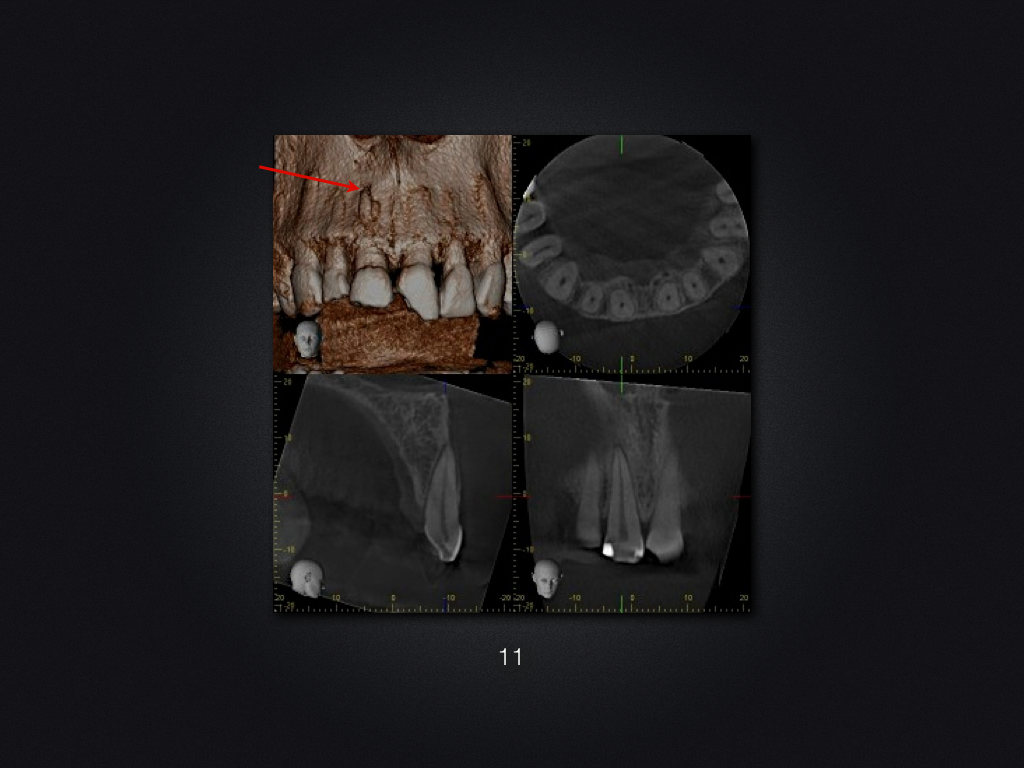

11 21 D.005

Trauma-„Zweitversorgung“